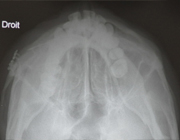

Clichés 2D de contrôle après réduction synthèse par plaque et greffe osseuse: